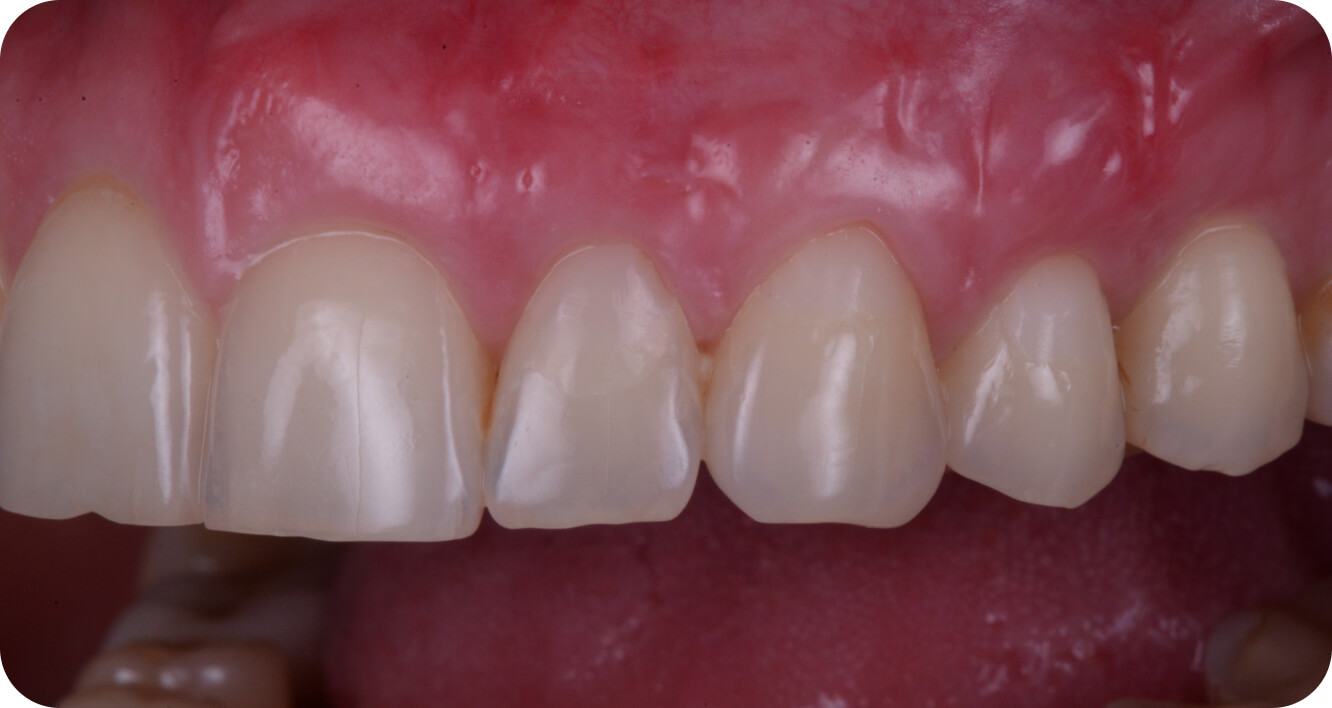

Мои работы

до/после

Большие

работы

Интересные

случаи

Пластика десны

оголенных корней